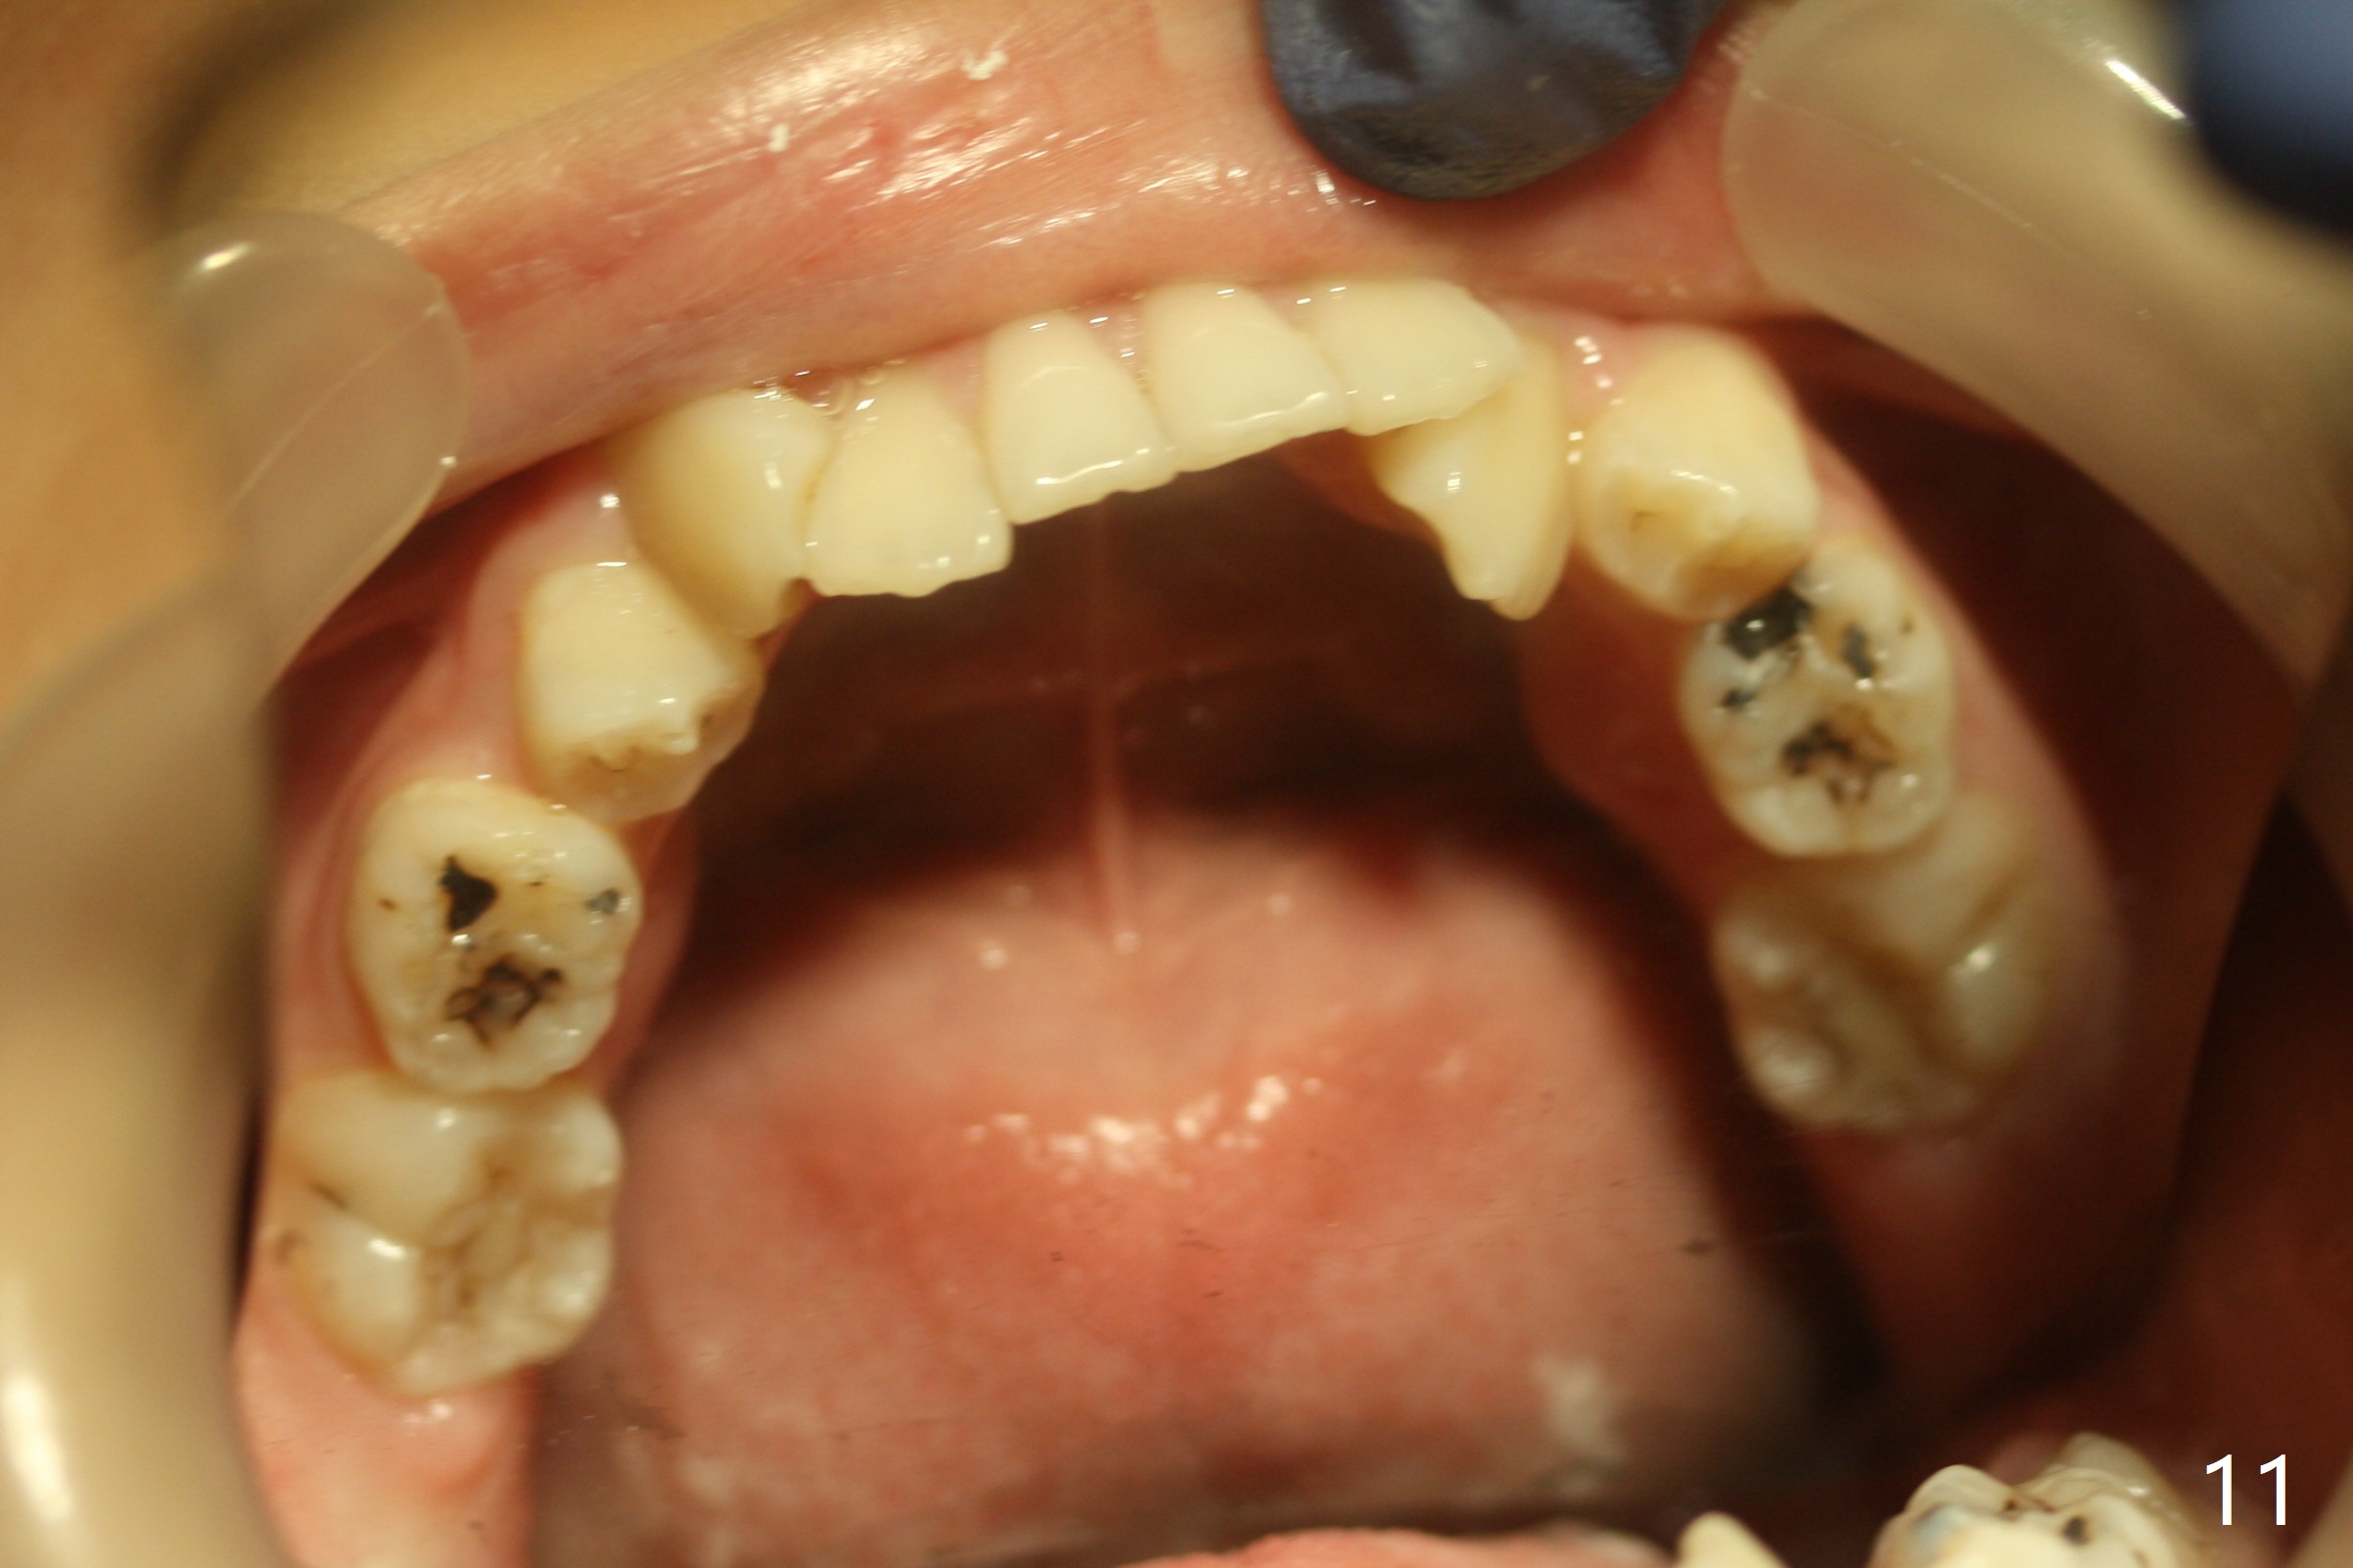

Severe crowding with normal facial profile appears to dictate extraction of 4 bicuspids and of the lower 2nd primary molars (Fig.1-11).  Since there is no time for banding before school, delay in orthodontic treatment post extraction will lose space?

Dear Dr. Shaughnessy: can you open the following link?  I would like to try to extract 4 bicuspids and 2 lower primary 2nd molars and let the canines shift by themselves.  But I wonder whether the 2nd permanent bicuspids, especially the upper ones, may shift mesially instead.  How would you like to handle the situation?